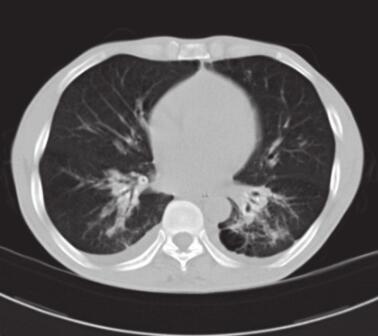

图3 肺部CT

两下肺可见片状模糊高密度影,纵隔及肺门可见多发肿大淋巴结,气管支气管软骨骨化